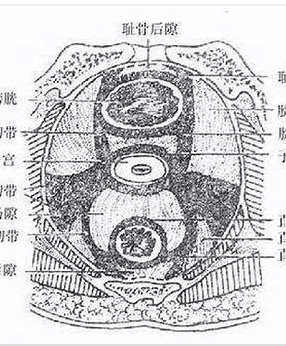

- 妇产康复―盆底结缔组织的功能解剖,三水平理论、三腔系统 布骨产后恢复中心 ,2020-04-19

- 发挥支撑作用的结缔组织包括盆腔内筋膜、盆腔韧带及会阴隔膜。盆腔内筋膜是腹横筋膜延续至覆盖骨盆底,位于盆底肌之上,腹膜之上,包绕盆腔脏器并将其连接至支持的肌肉组织和骨盆的骨组织。这一结缔组织网与盆腔脏器表面的结缔组织纤维相交织,使盆腔脏器固定在正常解剖位置。盆腔内筋膜的特殊部位增厚形成了盆腔韧带,参与.....

- 妇产康复---盆地结缔组织-韧带 布骨产后恢复中心 ,2020-04-19

- 盆筋膜脏层连续性强,像网状结构分布在整个盆腔,在某些部位局部增厚,附着于邻近的骨面形成韧带,它们起着支撑和固定脏器位置的作用,如耻骨膀胱韧带、子宫骶韧带等。有些韧带内有少许平滑肌纤维,如子宫圆韧带、子宫主韧带、子宫骶韧带等;有些韧带中有进出脏器的血管、神经穿行(又称血管神经鞘),如膀胱侧韧带、直肠侧.....

- 妇产康复---盆腔结缔组织-筋膜 布骨产后恢复中心 ,2020-04-19

- 骨盆筋膜为腹内筋膜向下直接延续的一部分,位于盆部腹膜与盆膈之间。覆衬盆壁的内面及盆底,并延续包被盆腔脏器、血管和神经,形成它们的鞘、囊和韧带,对盆内脏器具有保护和支持的作用。盆筋膜分为盆壁筋膜、盆膈筋膜和盆脏筋膜。在盆腔内相邻两脏器之间、盆内脏与盆壁之间盆脏筋膜形成4个筋膜隔,分别位于膀胱的前面、膀.....

- 妇产康复---盆底解剖结构及肌肉群 BuGu ,2020-04-19

- 盆底解剖结构,女性盆底是由封闭骨盆出口的多层肌肉和筋膜构成,有尿道、阴道和直肠贯穿其中。盆底肌肉群、筋膜、韧带及其神经构成了复杂的盆底支持系统,其互相作用和支持,承托并保持子宫、膀胱和直肠等脏器在盆腔的正常位置。若盆底结构和功能发生异常,可影响盆腔脏器位置及功能,甚至引起分娩障碍,而分娩处理不当,亦.....